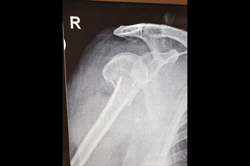

Shoulder Replacement